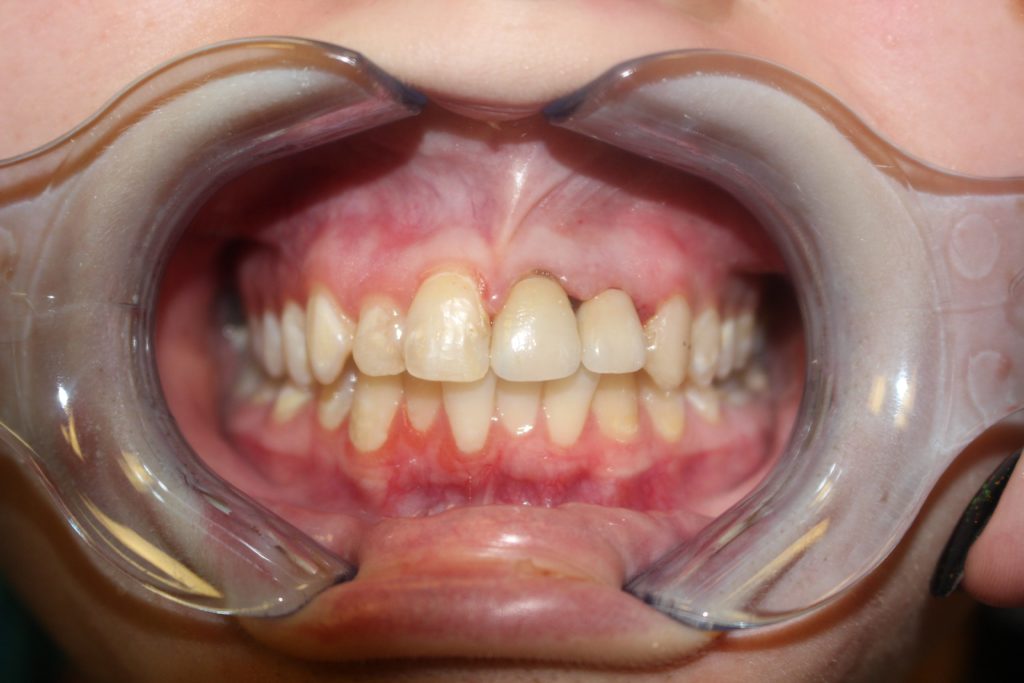

Smile Reveal #4

After gettingInvisalign, two anterior Crowns & Bioclear

After

We used Invisalign aligners and two anterior crowns and our patient’s smile has completely transformed. Definitely, a smile makeover that he will forever remember! You can also visit us at South Airdrie Smiles for a complete smile transformation.